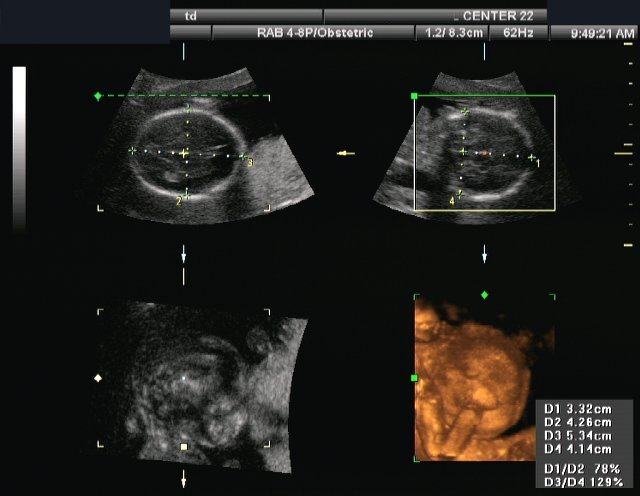

La ecografía 2D son las ecografías tradicionales en blanco y negro que probablemente hayas visto antes. Las imágenes muestran la estructura esquelética (esquema) del bebé. El género generalmente se encuentra fácilmente usando ultrasonido 2D. Si elige un ultrasonido de género 3D/4D, la parte de género se encontrará en 2D, luego comenzará la diversión 3D 4D por el resto de la sesión.

Las imágenes en 3D muestran el tejido del bebé, que se parece más a las imágenes reales. Podemos ver la redondez de la cara del bebé, la forma de la nariz y el contorno de los labios.El color en realidad no es el color del bebé, está mejorado por computadora para hacer que las imágenes sean más atractivas.

4D imagine muestral tejido del bebé mientras se mueve. ¡El ultrasonido 4D es cuando su bebé se mueve en tiempo real! Los videoclips en 4D de su bebé son similares a las imágenes en 3D, ¡pero en movimiento!